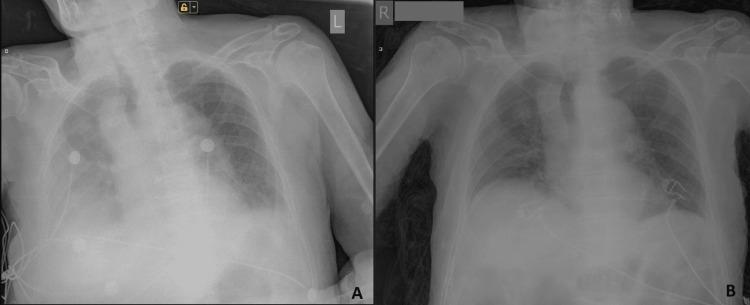

There are multiple factors associated with increased morbidity and mortality in COVID-19 patients, and advanced age is one such independent prognostic factor. It is well established that the multiorgan failure and death in COVID-19 patients are due to the hyperactivation of the NOD-, LRR- and pyrin domain-containing protein 3 (NLRP3) inflammasome and the ensuing cytokine storm. Colchicine, a well-known anti-inflammatory drug, has been shown to inhibit the NLRP3 inflammasome in micromolar concentrations potently. It has the unique property of accumulating in leukocytes, which is the primary cause of the abnormal activation of the NLRP3 inflammasome in COVID-19. It has been shown that achieving inhibitory concentrations of colchicine in leucocytes requires treatment with higher doses. Our recent studies showed that treatment with higher doses of colchicine in both outpatient and inpatient settings is safe and results in remarkable cure rates and significantly decreased mortality rates, even in the most severely affected patients with multiple comorbidities and risk factors. The main risk factor for severe COVID-19 is age, especially over 85 years. Here, we present a unique case of a 101-year-old male who underwent two major emergency abdominal surgeries and contracted COVID-19 while in the hospital. Laboratory tests showed increased values of markers for severe COVID-19, including CRP, D-dimer, and ferritin. Increased opacities bilaterally paracardially and moderate right-side pleural effusions were detected on the chest X-ray. We initiated our high-dose colchicine treatment regimen, resulting in the patient's complete recovery and discharge. We are convinced that the administration of high-dose colchicine to high-risk COVID-19 patients should be mandatory.

2019年冠状病毒病(COVID-19)患者发病率和死亡率增加与多种因素相关,高龄就是其中一个独立的预后因素。众所周知,COVID-19患者的多器官衰竭和死亡是由于含核苷酸结合寡聚化结构域样受体蛋白3(NLRP3)炎性小体的过度激活及随之而来的细胞因子风暴。秋水仙碱是一种著名的抗炎药物,已被证明在微摩尔浓度下能有效抑制NLRP3炎性小体。它具有在白细胞中蓄积的独特特性,而白细胞是COVID-19中NLRP3炎性小体异常激活的主要原因。研究表明,要在白细胞中达到秋水仙碱的抑制浓度需要使用更高剂量进行治疗。我们最近的研究表明,在门诊和住院环境中使用更高剂量的秋水仙碱进行治疗是安全的,即使在患有多种合并症和风险因素的最严重受影响患者中,也能取得显著的治愈率并显著降低死亡率。重症COVID-19的主要风险因素是年龄,尤其是85岁以上。在此,我们介绍一例独特病例,一名101岁男性在医院接受了两次紧急腹部大手术,并在住院期间感染了COVID-19。实验室检查显示,包括C反应蛋白(CRP)、D-二聚体和铁蛋白在内的重症COVID-19标志物值升高。胸部X线检查发现双侧心旁混浊增加以及右侧中度胸腔积液。我们启动了高剂量秋水仙碱治疗方案,患者完全康复并出院。我们坚信,对高危COVID-19患者应强制使用高剂量秋水仙碱。